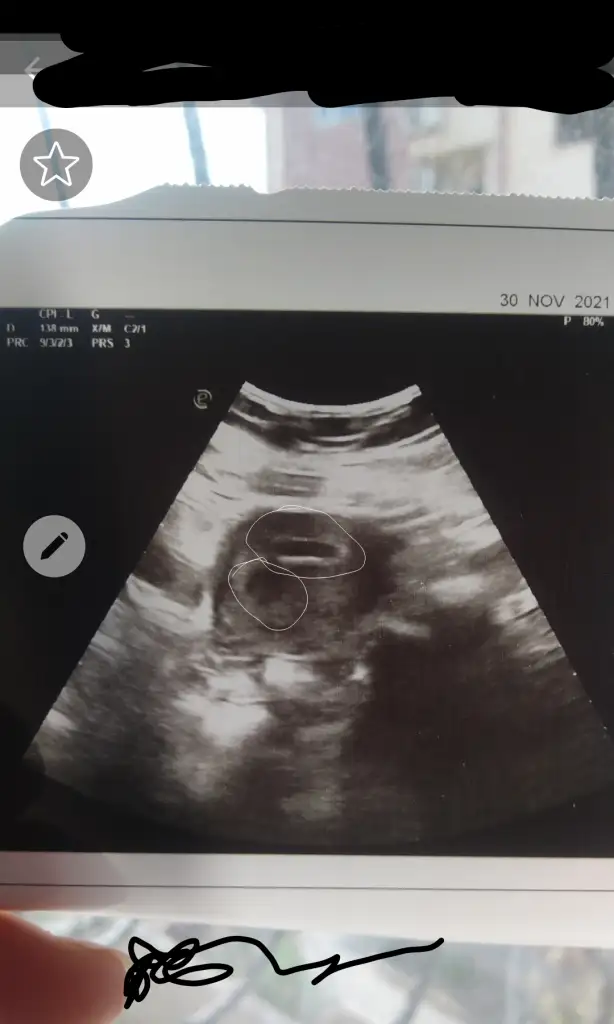

Kızlar kağıdımı yorumlayabilir misiniz yolk kesesi vs doktor 5 haftalık 10 mm dedi 2 hafta sonra kalp atışı için gel dedi başka bişey demedi

• Capture+_2021-12-02-12-34-13.webp

Capture+_2021-12-02-12-34-13.webp

18,5 KB · Görüntüleme: 219